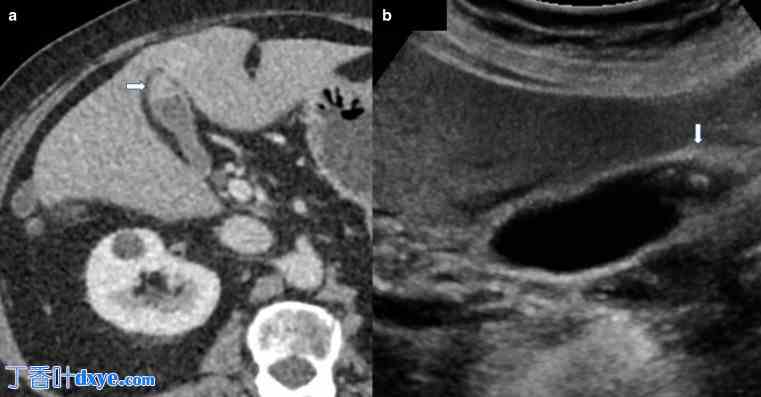

(a) 轴向增强 CT 显示胆囊底部局部不连续增厚,粘膜增强正常,这是胆囊底部腺肌瘤病的典型表现。 (b) 灰阶超声证实胆囊壁上有结节性强回声灶,导致粘膜窦中胆固醇晶体的混响伪影——典型的“彗星尾”伪影(白色箭头)。彗星尾伪影也可能是假息肉和胆固醇息肉的特征。